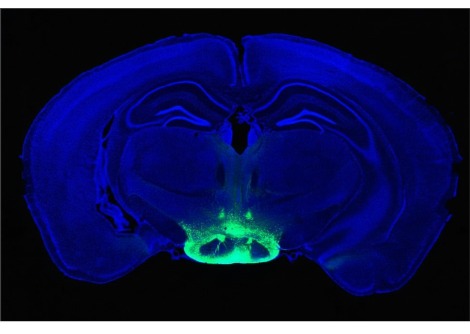

قام الباحثون بحقن المخاريط الوظيفية في شبكية عين 32 عين فأر ، والمخاريط الشاذة في 23 عينًا أخرى. في بعض الأحيان ، تلقت عين الفأر عمليات الزرع ، وأحيانًا واحدة فقط. كلا النوعين من المخاريط ، سواء كانا يعملان أم لا ، متصلان بشبكية العين لتكوين كتلة خلوية نموذجية للعين السليمة وضرورية للرؤية في الضوء الساطع.

لكن أوجه التشابه انتهت بمجرد أن عرّض الباحثون الفئران للضوء. استجابت شبكية عين الفئران ذات المخاريط البشرية الوظيفية للضوء أثناء اختبار العين المصمم لقياس هذا ، والمعروف باسم الرسم الكهربي الدقيق للشبكية ، بينما لم تستجب شبكية العين لدى أولئك الذين لديهم مخاريط مختلة وظيفيًا. في اختبار آخر ، اختارت الفئران التي تلقت المخاريط الوظيفية التراجع إلى غرفة مظلمة عندما أعطيت الخيار ، وهو مؤشر على أن الحيوانات الليلية كانت تستشعر الضوء وتتجنبه كما تفعل الفئران عادة. على النقيض من ذلك ، بقيت الفئران ذات المخاريط المعيبة في الضوء لجزء كبير من الوقت.